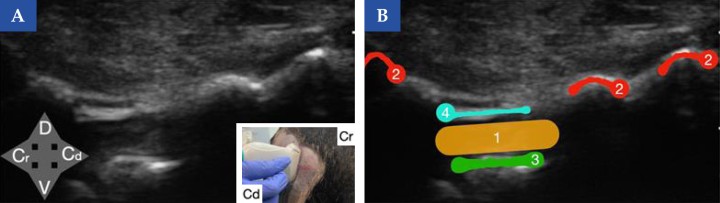

<b>Referencias ecográficas del espacio lumbosacro en el perro (vista transversal)</b>. (<b>A</b>) Imagen ecográfica encorte transversal obtenida con sonda lineal a nivel del espacio lumbosacro en un perro. En la imagen inferior derecha se muestra la posición de la sonda ecográfica en el animal (Cr, craneal y Cd, caudal). (<b>B</b>) Esquema de identificación de las principales referencias anatómicas: crestas ilíacas (2), suelo del canal vertebral (3) y ligamento amarillo (4). El sitio de inyección se localiza en el canal vertebral (1), guiado por estas estructuras de referencia. <b>¿Para qué usar esta técnica?</b>: Cirugía del tercio posterior y abdomen principalmente. Tratamiento de dolor crónico lumbosacro

Referencias ecográficas del espacio lumbosacro en el perro (vista transversal). (A) Imagen ecográfica encorte transversal obtenida con sonda lineal a nivel del espacio lumbosacro en un perro. En la imagen inferior derecha se muestra la posición de la sonda ecográfica en el animal (Cr, craneal y Cd, caudal). (B) Esquema de identificación de las principales referencias anatómicas: crestas ilíacas (2), suelo del canal vertebral (3) y ligamento amarillo (4). El sitio de inyección se localiza en el canal vertebral (1), guiado por estas estructuras de referencia. ¿Para qué usar esta técnica?: Cirugía del tercio posterior y abdomen principalmente. Tratamiento de dolor crónico lumbosacro